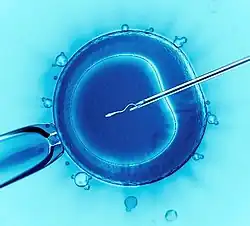

This image shows intracytoplasmic sperm injection, the most commonly used IVF technique. | |

IVF may be used to overcome female infertility when it is due to problems with the fallopian tubes, making in vivo fertilisation difficult. It can also assist in male infertility, in those cases where there is a defect in sperm quality; in such situations intracytoplasmic sperm injection (ICSI) may be used, where a sperm cell is injected directly into the egg cell. This is used when sperm has difficulty penetrating the egg. ICSI is also used when sperm numbers are very low. When indicated, the use of ICSI has been found to increase the success rates of IVF.

The sperm and the egg are incubated together at a ratio of about 75,000:1 in a culture media in order for the actual fertilisation to take place. A review in 2013 came to the result that a duration of this co-incubation of about 1 to 4 hours results in significantly higher pregnancy rates than 16 to 24 hours.[56] In most cases, the egg will be fertilised during co-incubation and will show two pronuclei. In certain situations, such as low sperm count or motility, a single sperm may be injected directly into the egg using intracytoplasmic sperm injection (ICSI). The fertilised egg is passed to a special growth medium and left for about 48 hours until the embryo consists of six to eight cells.

Sperm selection

Intracytoplasmic sperm injection (ICSI) is where a single sperm is injected directly into an egg. Its main usage as an expansion of IVF is to overcome male infertility problems, although it may also be used where eggs cannot easily be penetrated by sperm, and occasionally in conjunction with sperm donation. It can be used in teratozoospermia, since once the egg is fertilised abnormal sperm morphology does not appear to influence blastocyst development or blastocyst morphology.[75]